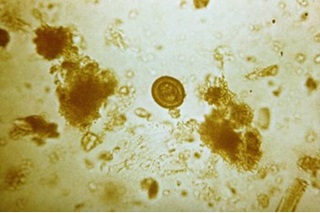

2. Trứng

Trứng của sán heo rất giống sán dải bò, trứng hình cầu, màu vàng xám, bên trong là khối nhân có hạt, chiết quang nằm trong nhân, có vỏ dày có đường kính khoảng 35 µm, bên trong chứa phôi 6 móc[1].

Trứng sán Taenia saginata và Taenia solium (Nguồn: PHIL 4832 - CDC)